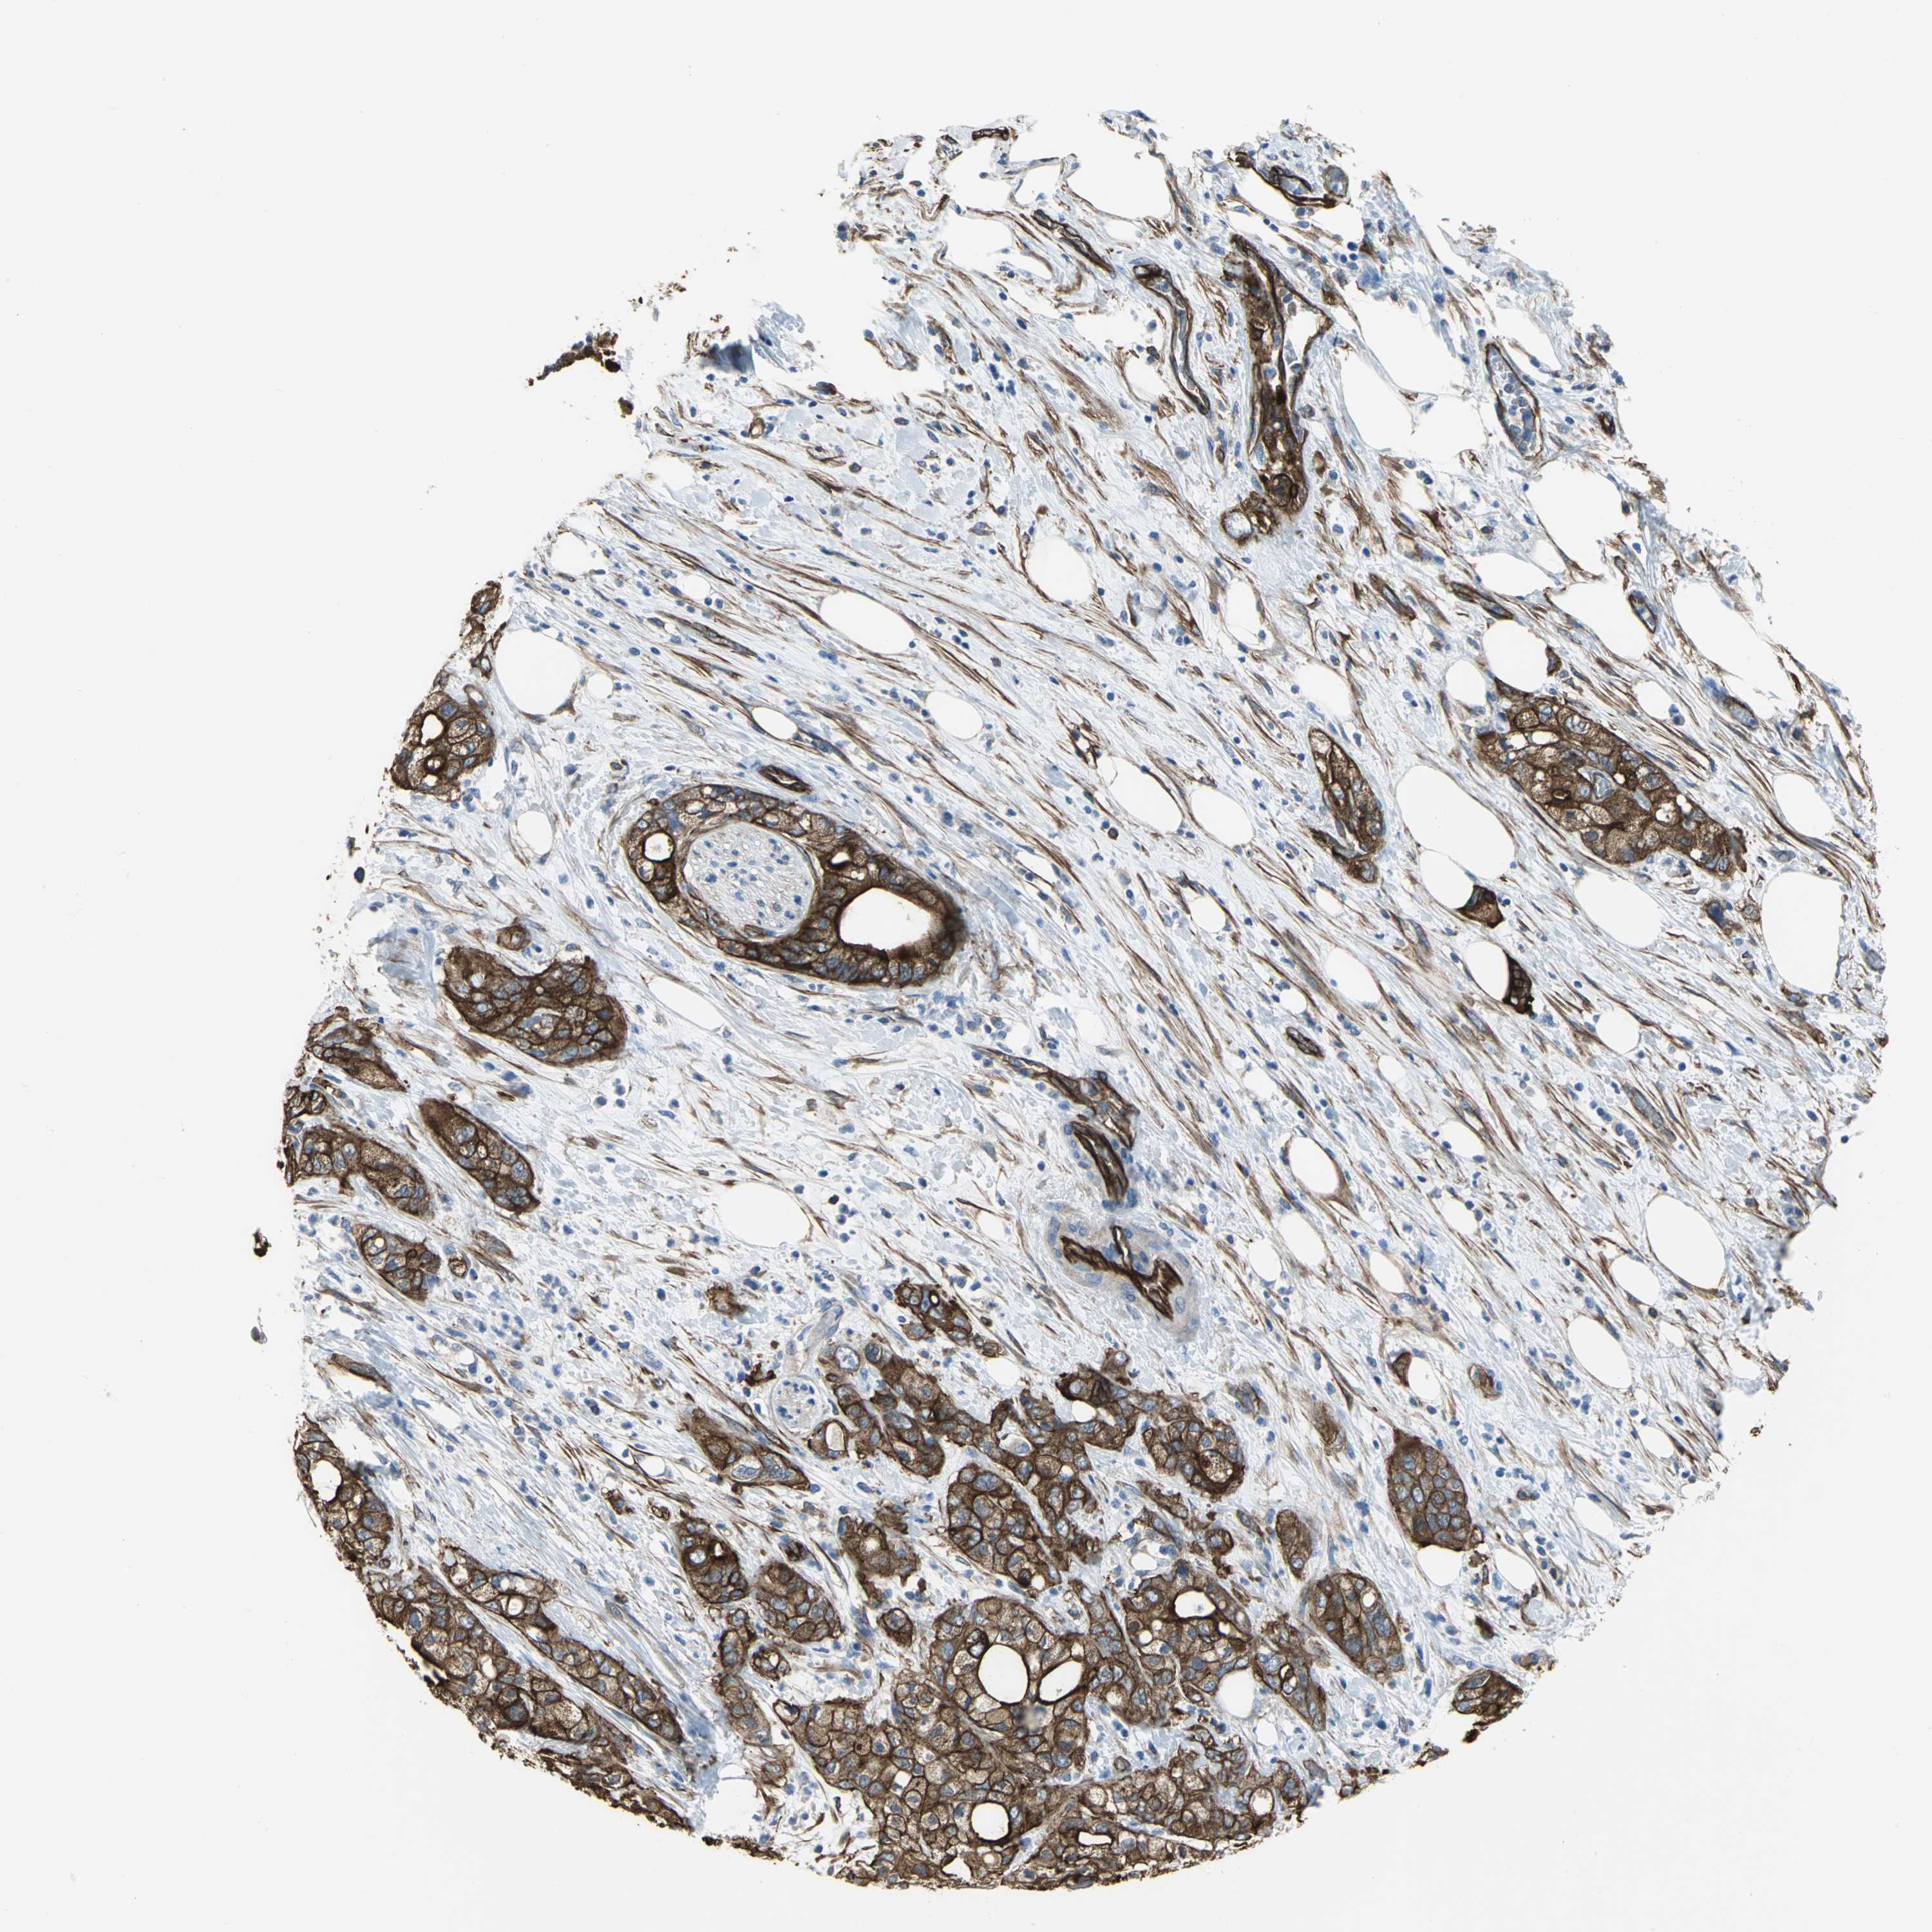

PANCREATIC CANCER - Protein expressioni

A mouse-over function shows sample information and annotation data. Click on an image to view it in a full screen mode. Samples can be filtered based on level of antibody staining by selecting one or several of the following categories: high, medium, low and not detected. The assay and annotation is described here.

Note that samples used for immunohistochemistry by the Human Protein Atlas do not correspond to samples in the TCGA dataset.

Antibody stainingi

Antibody staining in the annotated cell types in the current human tissue is reported as not detected, low, medium, or high, based on conventional immunohistochemistry profiling in selected tissues. This score is based on the combination of the staining intensity and fraction of stained cells.

Each image is clickable and will lead to virtual microscopy that enables deeper exploration of all samples and also displays staining intensity scores, fraction scores and subcellular localization as well as patient and tissue information for each sample.

Antibody HPA004747

Antibody HPA004886

Antibody CAB019322

Staining

High

Medium

Low

Not detected

Intensity

Strong

Moderate

Weak

Negative

Quantity

>75%

75%-25%

<25%

None

Location

Nuclear

Cytoplasmic/membranous

Cytoplasmic/membranous,nuclear

Adenocarcinoma, NOS

Adenocarcinoma, metastatic, NOS